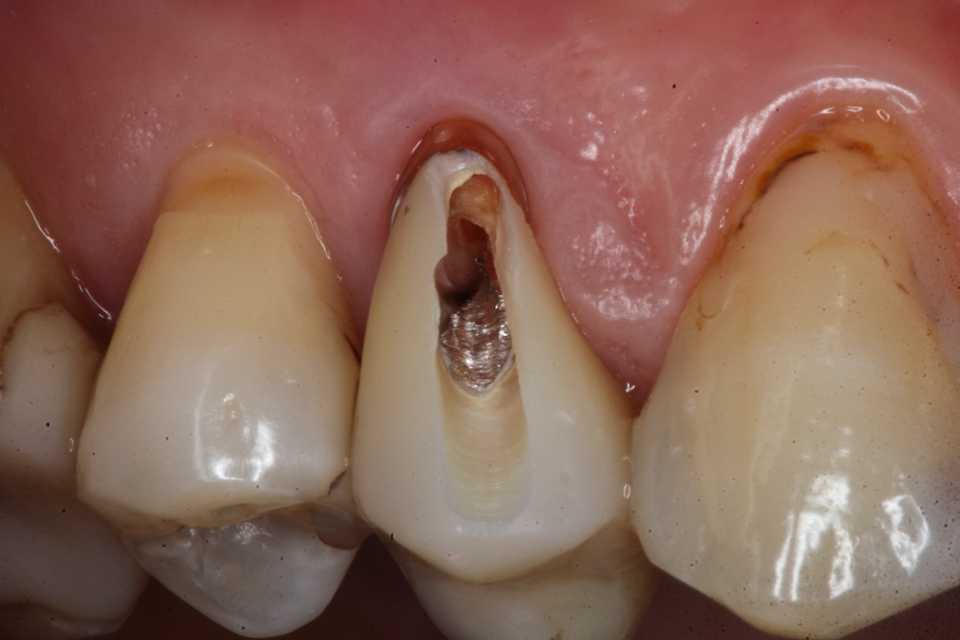

40代女性、右上4、Per+GAPerというのは根管治療後に根管内に感染を起こしている状態でGAとは炎症が根管の外に波及している状態。この方は10年程前に神経を取って被せたということでしたが、2、3年前GAができて別の歯医者に行ったら切って膿を出してもらったら治ったということでしたが、根管に細菌が感染している以上細菌が消えたりしないので、何度も再発します。今回は切開というよりは根管内部に3MIX+α-TCPを入れて根管内部を消毒殺菌しようというコンセプト。内部のポストも根管充填材も完全に除去する必要はない。根管充填材が見えるところまで穴を開けて薬剤を入れ、CRで蓋をするだけでよい。信じられないだろうが、これだけで治る。もし再発するようなら、冠のどこかに隙間があり、そこから細菌が出たり入ったりしているわけだから、冠もポストも除去して隙間を塞ぐ必要がある。多分従来の根幹治療しか知らない歯科医師は何が起こっているのか分からないと思うが、根管治療の真実が分かれば理解できないことはないと思う。一般に思われてる根管治療というのは理想からは程遠いものだということだ。冠にもポストにも根管充填材にも隙間だらけで細菌がその隙間から出入りしているのが現実だ。

僕が使っているボンディング材は​ こちら ​。α-TCPの50%クエン酸練り(硬化する)。

この上からCRダイレクトボンディングでカバーする。​ 3MIX+α-TCP

では時系列でどうぞ